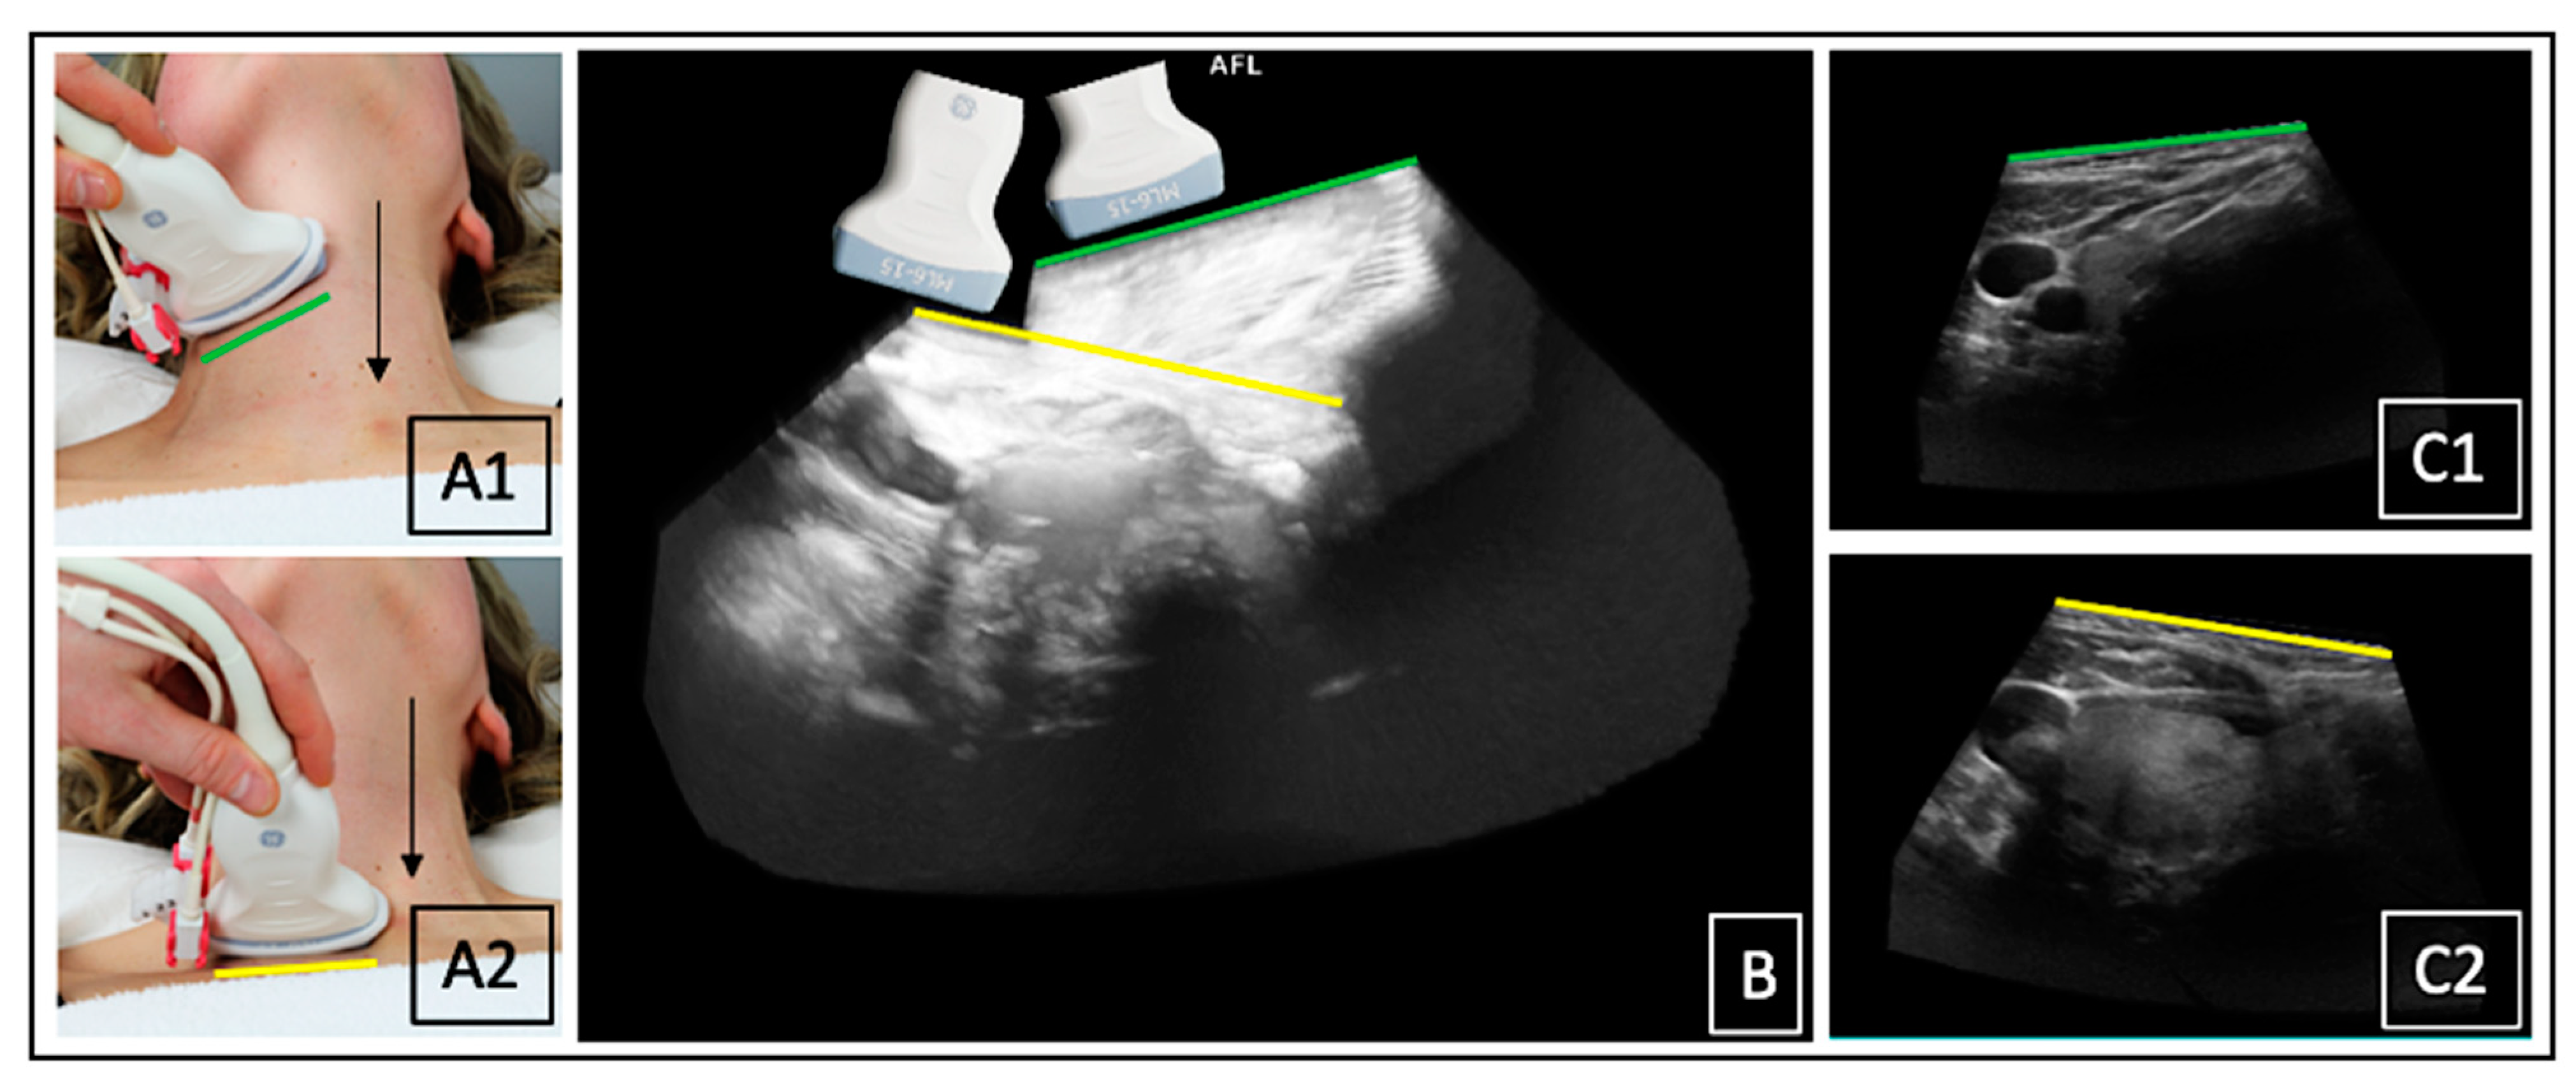

The larynx was found to be an influencing factor in the acquisition process of 3D-US in general. In order to capture the thyroid at any height, the probe had to be moved around the larynx, resulting in a tilt of the 3D data sets. This was a challenging factor for the stitching process (Figure 8).

Figure 8.

Probe tilted laterally above the larynx (A1) and medially below the larynx (A2); tilt shown in the 3DsnUS data set of the right thyroid lobe (B); tilt laterally (C1) and medially (C2) in the corresponding single transverse slices of the 3DsnUS scan.